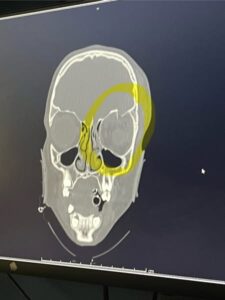

Against all odds, and thanks to the swift action of first responders and the expertise of the medical teams in Austin, Sophia Martinez’s life was miraculously saved. The successful management of the brain bleed and swelling is a profound testament to modern medicine, allowing her family to breathe a collective sigh of relief that their daughter is still with them. However, the ordeal is far from over. The physical toll of the impact was devastating, and doctors have confirmed that Sophia will require major reconstructive surgery above her eye. This ongoing physical battle is a stark reminder of how quickly an ordinary moment can lead to long-term trauma. The need for specialized surgery introduces a new layer of complexity, demanding further resilience from Sophia and placing an inevitable emotional and financial strain on her loved ones as they navigate the long road to recovery.